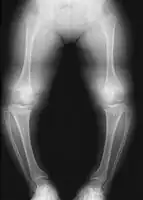

- Varus (bowleg) or valgus (knock knee) deformities

Radiologic findings

A skeletal survey is useful to confirm the diagnosis of achondroplasia. The skull is large, with a narrow foramen magnum, and relatively small skull base. The vertebral bodies are short and flattened with relatively large intervertebral disk height, and there is congenitally narrowed spinal canal. The iliac wings are small and squared, with a narrow sciatic notch and horizontal acetabular roof.[15][16] The tubular bones are short and thick with metaphyseal cupping and flaring and irregular growth plates.[15] Fibular overgrowth is present. The hand is broad with short metacarpals and phalanges, and a trident configuration. The ribs are short with cupped anterior ends.[15] If the radiographic features are not classic, a search for a different diagnosis should be entertained. Because of the extremely deformed bone structure, people with achondroplasia are often "double jointed". The diagnosis can be made by fetal ultrasound by progressive discordance between the femur length and biparietal diameter by age. The trident hand configuration can be seen if the fingers are fully extended.